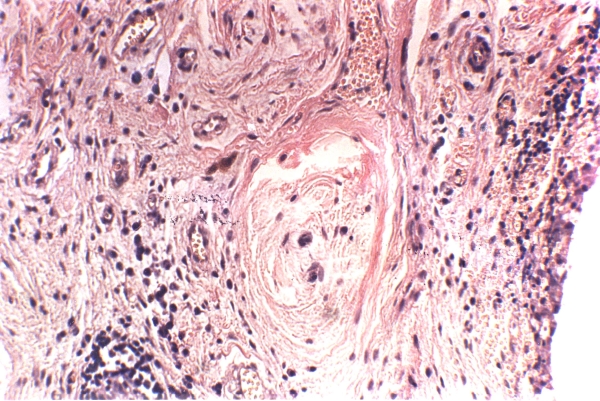

Восстановление хрящевой ткани происходит благодаря накоплению хондробластов, которые превращаются в хондроциты. Эти клетки заполняют поврежденные участки хряща, восстанавливая его целостность и увеличивая объем движений в пораженном суставе.